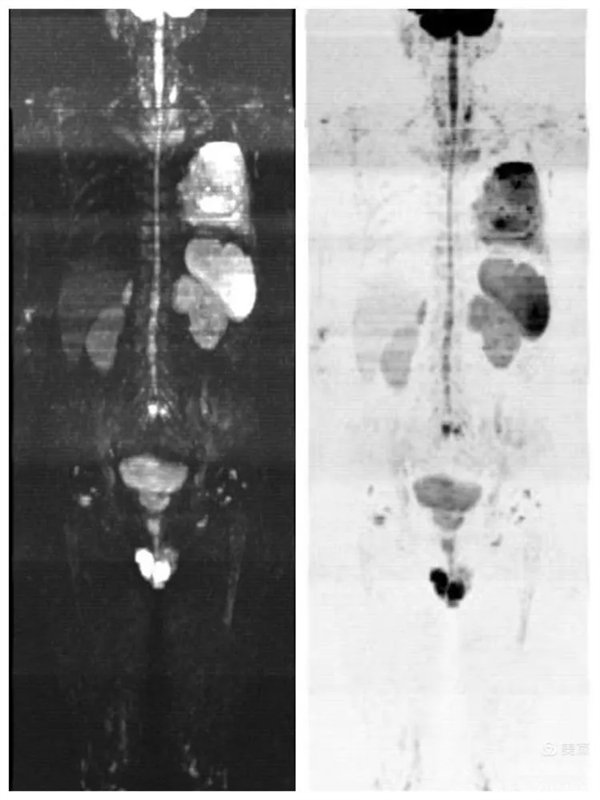

圖4:彌散成像圖與類PET圖組合

磁共振全身彌散加權(quán)成像(WB-DWI),是將彌散加權(quán)成像技術(shù)與自動拼接技術(shù)和全景成像矩陣相結(jié)合而獲得全身的彌散加權(quán)成像影像。所得影像經(jīng)黑白翻轉(zhuǎn)后可達(dá)到與正電子發(fā)射計(jì)算機(jī)體層顯像(PET)影像類似的效果,故被稱為“類PET”,是近年來發(fā)展起來的全新影像檢查新技術(shù)。

該技術(shù)能夠進(jìn)行全身大范圍掃描,并加以3D后處理重建,可獲得全身腫瘤篩查、良惡性腫瘤的鑒別、腫瘤TNM分期及療效隨診等診斷信息,全身彌散技術(shù)把肌肉、脂肪、肝臟等組織背景信號抑制掉,突出了病變的顯示,大大提高了病變組織尤其是惡性腫瘤及其轉(zhuǎn)移灶的檢出率。